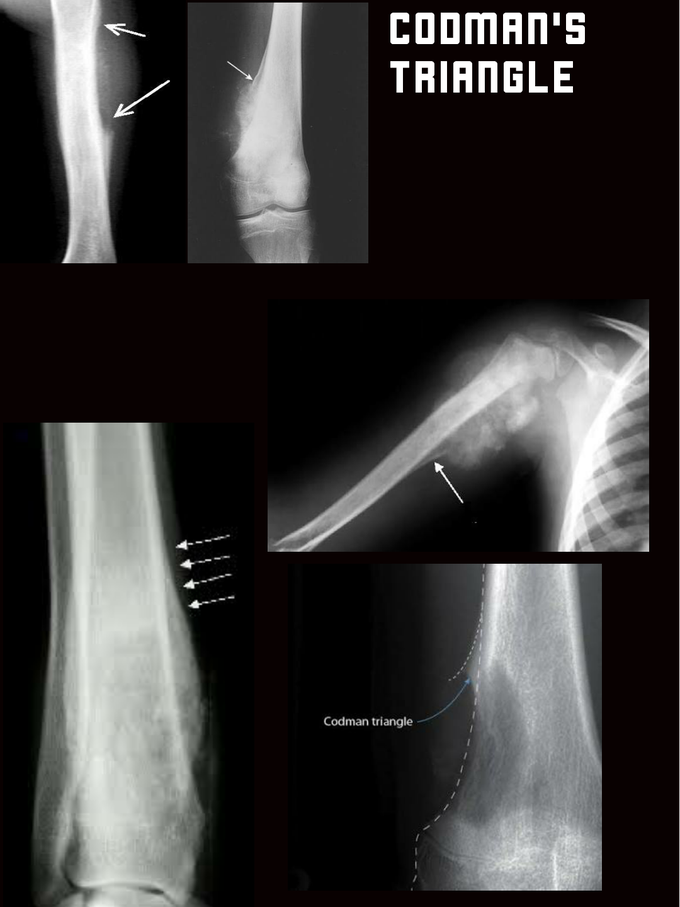

Conselho Nacional de Técnicos e Tecnólogos em Radiologia - Triângulo de Codman é um termo usado para descrever a área triangular de novo osso subperiosteal que é criada quando uma lesão, frequentemente

Medvet.diagnostico - *Região de rádio distal* O Triângulo de Codman é uma reação periosteal triangular que resulta da elevação do periósteo, sendo geralmente associado a neoplasia óssea primária, e menos frequentemente, a

CODMAN'S TRIANGLE - Radiology Classroom | Facebook